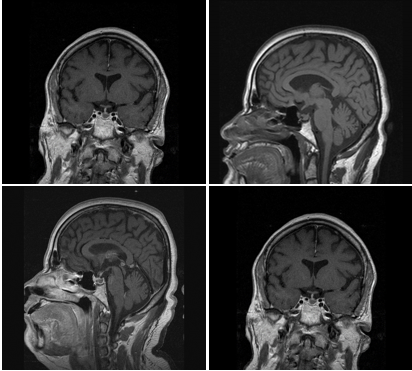

MRI Diagnosis

Conclusion: findings are consistent with post-operative changes? Ischemia of small vessel disease